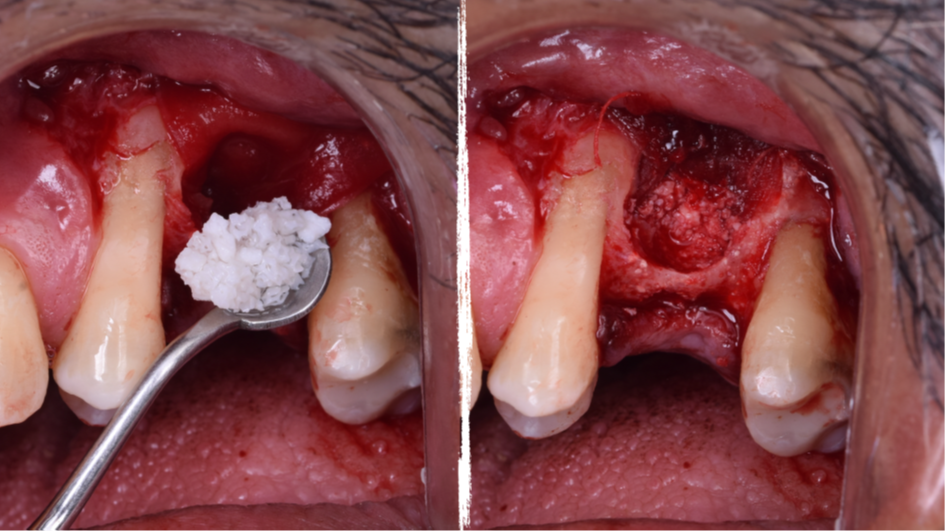

O presente trabalho tem como objetivo fazer um relato de caso clínico de reintervenção em enxerto ósseo para levantamento de seio maxilar pela técnica da janela lateral com instalação simultânea de implante Maestro Superiore.